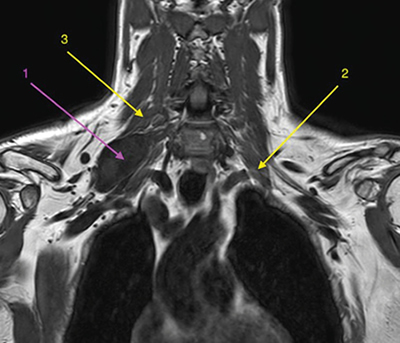

Los schwannomas de plexo braquial son tumoraciones desarrolladas a partir de las vainas neurales de rara presentación, pero evolución benigna. Pueden ocasionar clínica, generalmente de tipo neuropático, por crecimiento local con el consiguiente efecto compresivo de estructuras neurales nobles como las raíces del plexo braquial.

Presentamos el caso de un paciente diagnosticado de schwannoma de plexo braquial con efecto compresivo creciente, a quien se le plantea tratamiento con toxina botulínica en los músculos escalenos.

Brachial plexus schwannomas are tumors developed from the neural sheaths of rare presentation, but benign evolution. They can cause symptoms, generally of the neuropathic type, due to local growth with the consequent compressive effect of noble neural structures such as the roots of the brachial plexus.

We present the case of a patient diagnosed with brachial plexus schwannoma with increasing compressive effect who was treated with botulinum toxin in the scalene muscles.